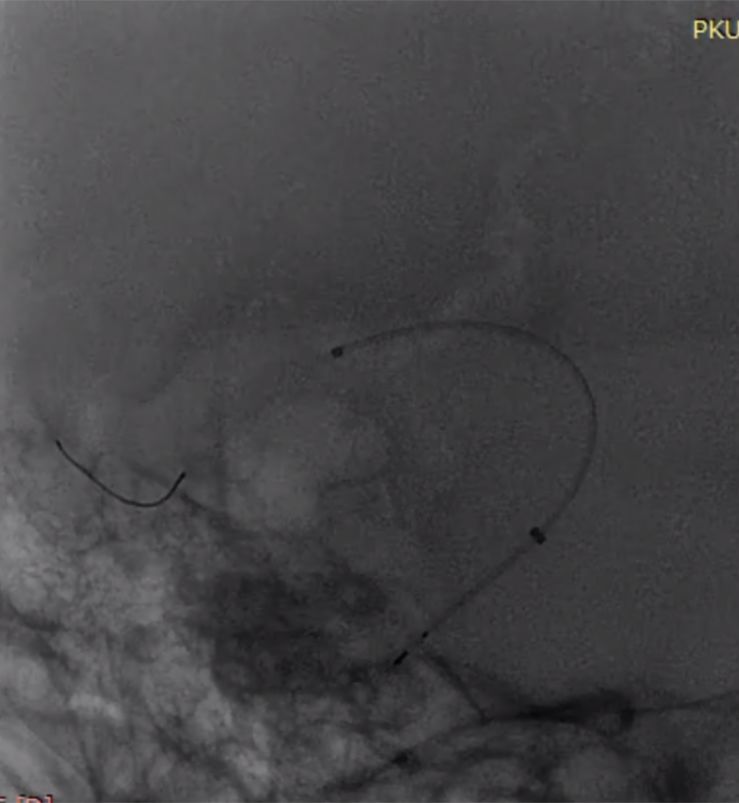

全身麻醉下右侧股动脉入路,造影选取工作位。

(1)Synchro微导丝携带Marksman支架管送入大脑中动脉,沿支架管送入3.5mm×35mmPED一枚,于M1段开始释放,可见释放后回缩明显,支架管在回收过程中支架再次短缩(图4)。

滑动查看更多

图4

(2)第二枚PED4.5mm×35mm桥接第一枚支架,释放过程中第一枚支架稳定,第二枚支架回缩同样明显(图5)。

图5

(3)第三枚PED 5mm×35mm桥接,可见近端已着陆于相对正常血管,但支架长度明显长于35mm,且近端血管转折处仍可见瘤样改变(图6)。

图6

(4)第四枚PED 5mm×35mm桥接第三枚支架,开始释放时贴壁不良,继续推出一段后支架展开,海绵窦垂直段支架展开形态欠佳,回收后推送形态不变,考虑存在狭窄(图7)。

图7